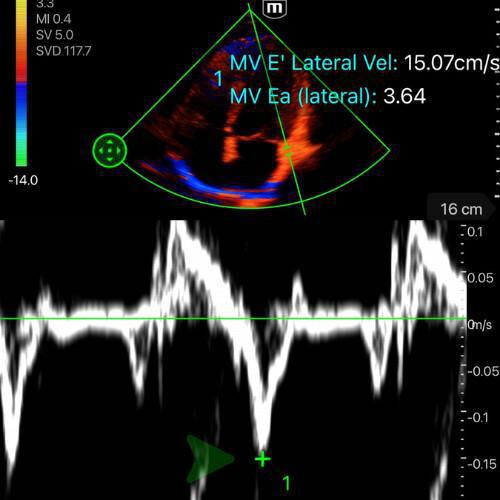

🔧 Comment mesurer E/E’

- Mesurer l’onde E comme décrit ci-dessus (si déja fait, la machine retient la valeur)

- En A4C, placer le curseur sur l’anneau mitral, en latéral

- Activer le mode Doppler tissulaire (TDI).

- Chercher la premiere onde négative apres le onde S' – c'est l'onde E’ (cf. vidéo/photo ci-dessous)

- Mesurer la vitesse maximale de E’. La machine fait le calcul du rapport pour vous.

-

E/E’ < 8, PRVG basses : le cœur tolérera un remplissage, et une hypovolémie est possible.

E/E’ > 14, PRVG hautes : tout apport hydrique risque d’aggraver la congestion ou de précipiter un œdème pulmonaire.

E/E’ 8–14, zone grise : l’interprétation dépend du contexte (tachycardie, sepsis, IC chronique, ventilation mécanique). Le chiffre seul ne suffit pas à guider la prise en charge.

![]()